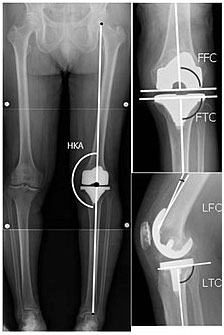

HKA: Hip-knee-ankle angle

FFC: frontal femoral component angle

FTC: frontal tibial component angle

LFC: lateral femoral component angle

LTC: lateral tibial component angle

Knee replacement is routinely evaluated by X-ray, including the following measures:

- - HKA: Hip-knee-ankle angle, which is ideally between 3° varumto 3° valgum from a right angle.

- - FFC: frontal femoral component angle. It is typically regarded as optimal when being 2–7° in valgus.

- - FTC: frontal tibial component angle, which is regarded as optimal when being at a right angle. A varus position of more than 3° has generally been found to increase the failure rate of the prosthesis.

- - LFC: lateral (or sagittal) femoral component angle

- - LTC: lateral (or sagittal) tibial component angle, which is ideally positioned so that the tibia is 0–7° flexed compared to at a right angle with the tibial plate.